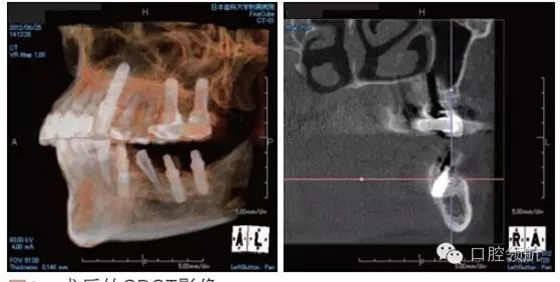

利用曲面斷層及CBCT檢查埋入部位情況,雖未出現(xiàn)與主訴相關的神經損傷,但無意中卻發(fā)現(xiàn)了種植體的舌側穿孔(圖1、圖2)。

圖2 術后的CBCT影像。

雖不能確定是裂鉆備洞還是植入種植體所造成的穿孔,但從4個月的病情的發(fā)展看,考慮可能是術中的舌下動脈損傷導致口底軟組織內出血而造成的感覺異常。采用常規(guī)藥物及物理療法開始進行治療。